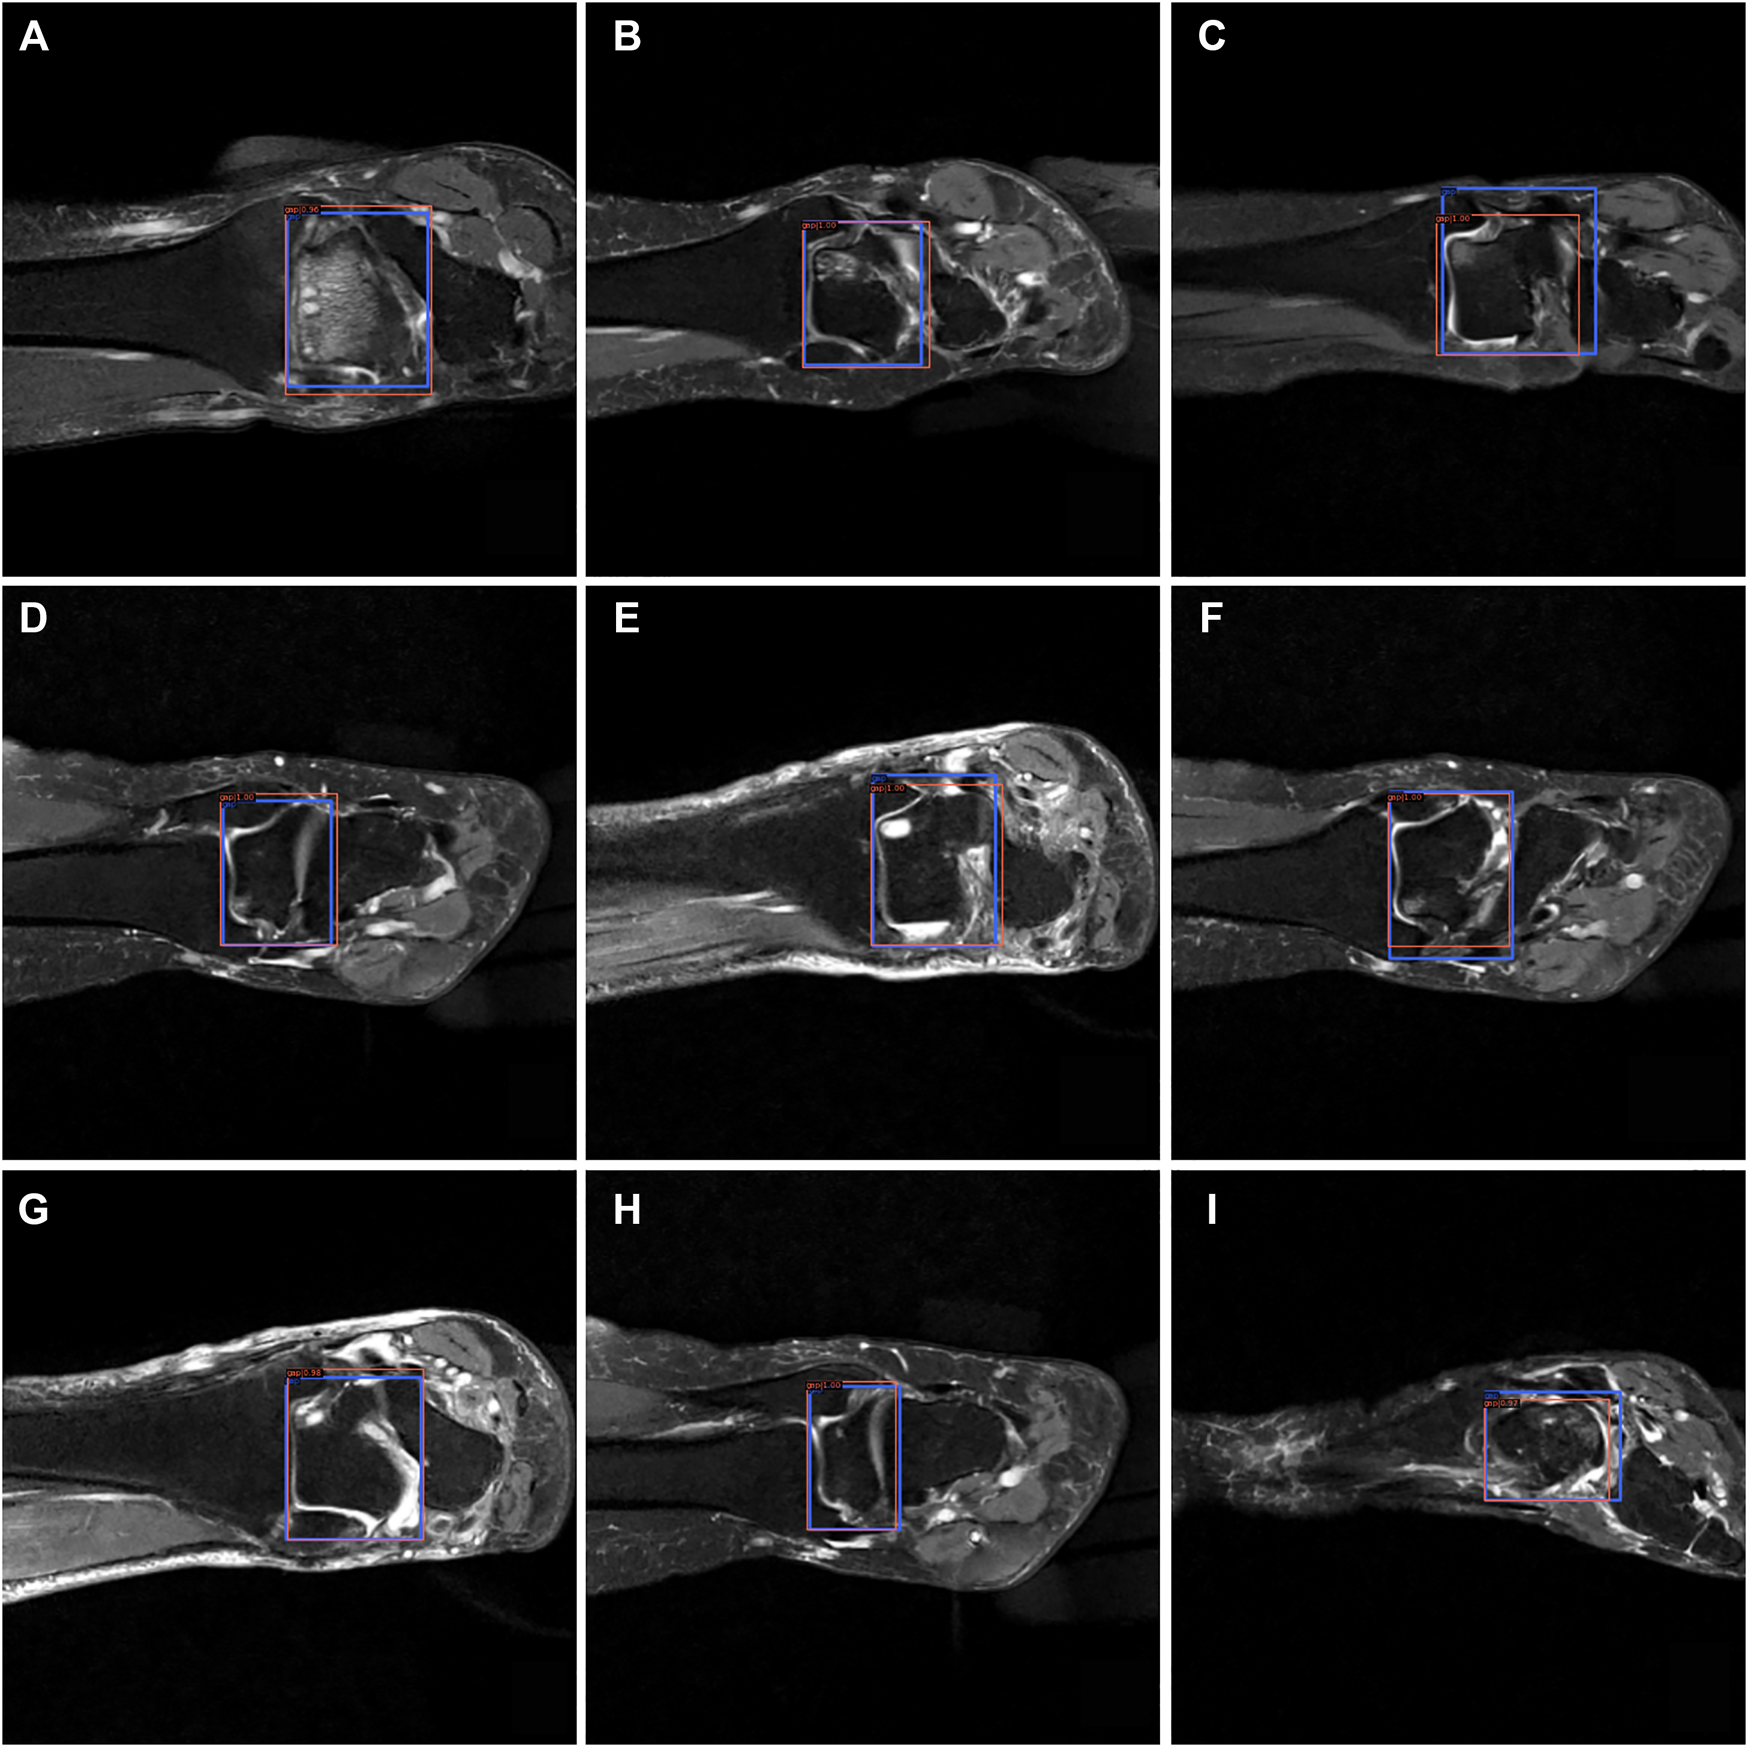

From Figures 7–9, we could intuitively observe that our network provided a comparable detection result (red bounding boxes) with that of senior radiologists (blue bounding boxes). Noticeably, our model achieved stable detection results on all three detection tasks, which shows the effectiveness of our method. More examples are shown in the Supplementary Figures S1–S3.

FIGURE 8

The bounding box visualization. Prediction result (red) vs. the ground truth (blue) of the talus gaps. All the images (A–I) were selected from testing group to determine the AI recognition accuracy of talus gap. AI detection result was labeled by red rectangular. The ground truth was manually depicted and labeled by blue rectangular.